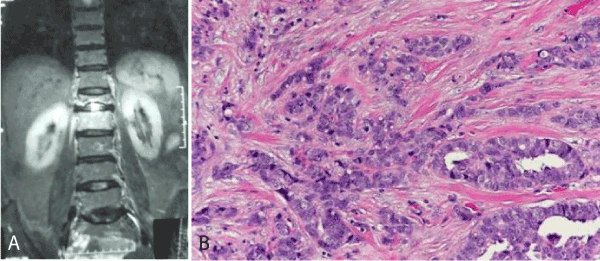

Of the 4 cases of metastatic lesions in our study, epithelial malignancies were most common (3 cases, 2.9%) to metastasize followed by soft tissue malignancy (Figure 3a,b). The primary sites for the epithelial metastasis were from breast, colon and kidney. The prevalence of multiple primary epithelial malignant neoplasms varies from 0.734% to 11.7%. The case of metastatic soft tissue tumour was of, 13 year old female patient who presented with difficulty in walking. Patient had pathological fracture neck femur and greater trochanter. Biopsy revealed features of Liposarcoma. Extensive immunohistochemical staining was performed. The tumour cells were immune-negative for S-100 protein, CDK- 4, CD 68, CD 163, Cytokeratin, EMA, Melan A, LCA, Desmin, SMA, Calretenin, Inhibin, Synaptophysin and Chromoganin A. Thus ruling out other differential diagnosis, the features were compatible with a pleomorphic liposarcoma metastasizing to the bone.

Figure 3. Metastatic deposits of malignancy

Figure 3a. MRI spine showing sclerosis and lytic lesion at T12 vertebrae

Figure 3b. Photomicrograph showing metastasis of invasive ductal carcinoma of breast in bone. (Hematoxyilin  and  eosin stain 40x)